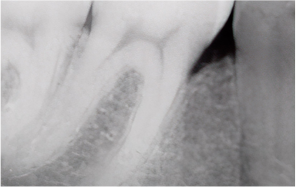

심한 치주질환으로 잇몸이 내려앉고 치조골이 흡수된 경우에도

엠도게인을 이용한 ‘잇몸재생술’을 통해

치아를 보존할 수 있습니다.

이 술식은 손상된 잇몸뼈와 주변 조직을 재생시키는 치료로,

엠도게인이라고 하는 잇몸조직을 재생시키는

주사를 사용하여 치아의 지지 구조를 다시 세워줍니다.

그 결과 치아를 뽑지 않고 기능과 건강을 회복할 수 있도록 돕습니다.

치조골 결손부 골이식술 효과

만성 치주염으로 손상된 치조골 재생에 도움

치아 주변 조직·치조골·치주인대 회복